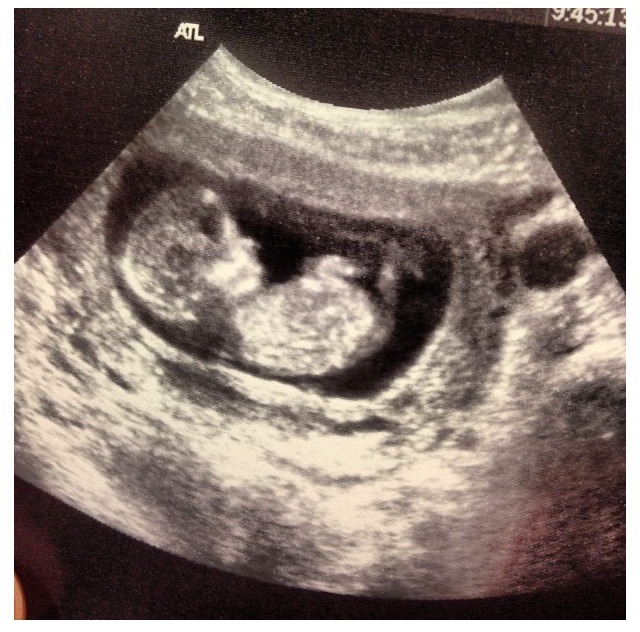

She said everything looked great but I do not remember her measuring the fold. I have a 14 week scan where I think I see the nasal bone but I'm not 100% sureAttachment 12667

I know they also look for nasal bones as a soft marker, too...your baby has a pretty nose, so that should give you some comfort...lol.